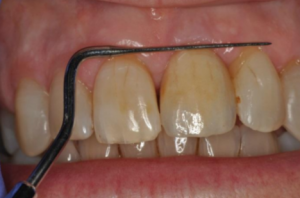

The patient presented to Dr. Tom with an over-erupted, discoloured upper left central incisor. She has a high lip line and all her front teeth and gums show with her smile. The patient had previously been informed that the pulp chamber and canal had become calcified. Her dentist had tried to find the canal but, unfortunately, had perforated through the buccal surface of the root subgingival. This has resulted in infection. At this time, I knew it was going to become very interesting and I was curious as to what could be done.

With further exploration of the tooth with photos, X-rays and periodontal probing, the complications were highlighted and were summarised as:

– Gingival recession of 5 mm